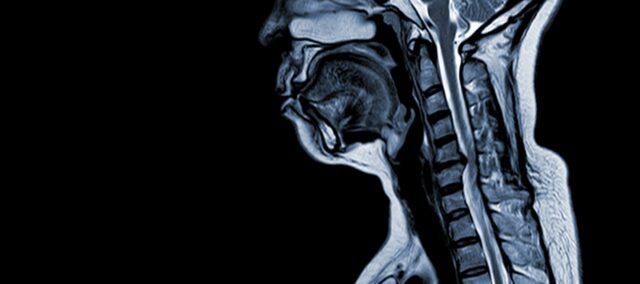

Cervikal spondylotisk myelopati (CSM) er en neurologisk tilstand, som er den hyppigste årsag til rygmarvsskader hos voksne. Enkelt sagt er der tale om kompression eller beskadigelse af rygmarven i nakken, primært på grund af den naturlige aldringsproces, der påvirker halshvirvlerne. Udtrykket 'myelopati' stammer fra de græske ord 'myelon', som betyder 'rygmarv' og 'pathos', som betyder 'sygdom'.

Patofysiologi

- Degeneration af diskus (udbuling af diskus): CSM begynder ofte med degeneration af intervertebrale skiver i halshvirvelsøjlen, hvilket får dem til at bule ud eller stikke ind i rygmarvskanalen.

- Subperiostal knogledannelse (ventral for rygmarvskanalen): Som reaktion på den øgede mekaniske belastning danner kroppen nyt knoglevæv på den forreste (ventrale) side af rygmarvskanalen, hvilket potentielt indsnævrer pladsen til rygmarven.

- Ossifikation af posterior longitudinal ligament: Det bageste langsgående ledbånd kan forbenes, hærdes og forkalkes, hvilket bidrager til indsnævring af rygmarvskanalen.

- Hypertrofi af Ligamentum Flavum: Hypertrofi af Ligamentum Flavum får det til at blive tykkere og mindre fleksibelt, hvilket yderligere indskrænker pladsen i rygmarvskanalen og komprimerer rygmarven.

Disse strukturelle ændringer fører samlet set til kompression og indsnævring af rygmarvskanalen, hvilket resulterer i de karakteristiske symptomer og komplikationer, der er forbundet med CSM. Anerkendelse af disse risikofaktorer og forståelse af de patofysiologiske mekanismer, der er involveret, er afgørende for både forebyggelse og behandling. Tidlig diagnose og passende indgreb er afgørende for at afbøde virkningerne af disse strukturelle ændringer på rygmarven.